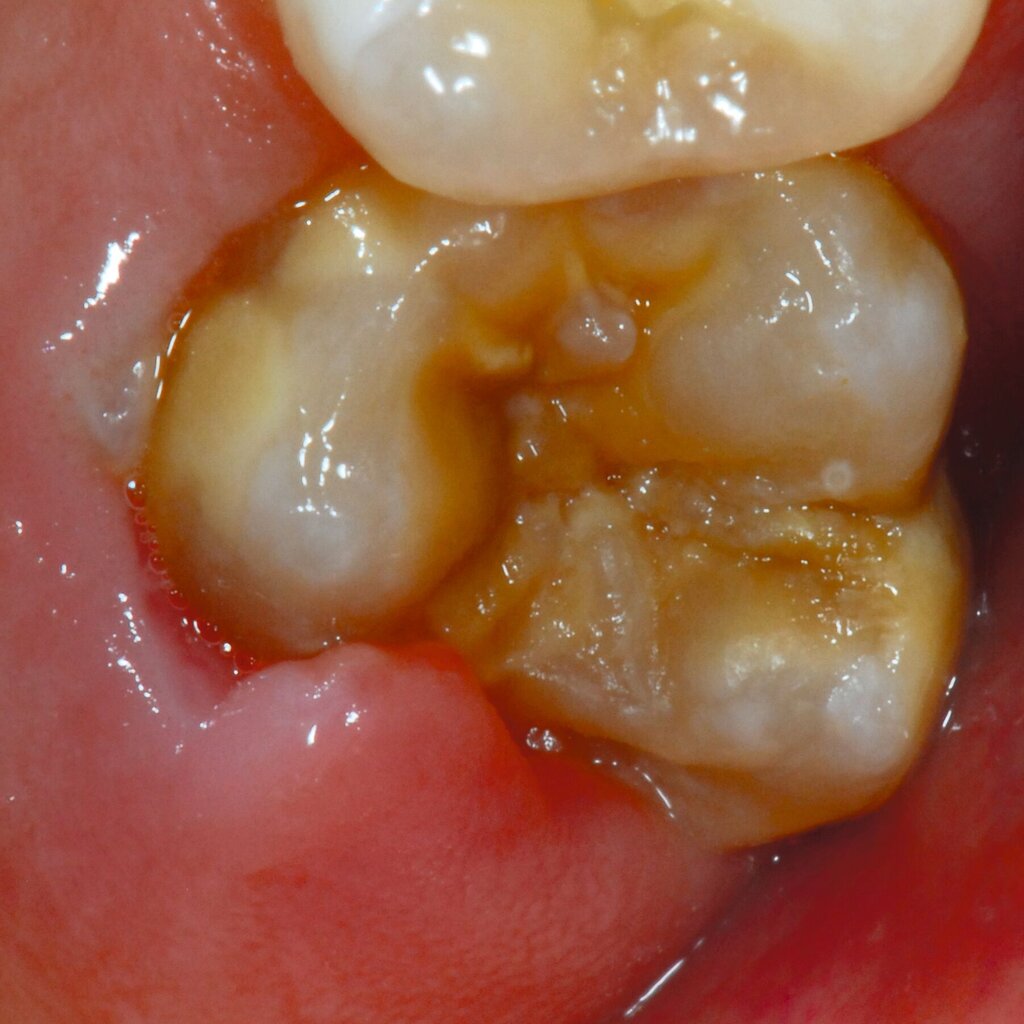

Das klinische Erscheinungsbild an bleibenden Zähnen zeigt typischerweise weißlich-gelbe bis gelblich-braune Opazitäten, die zumindest in einigen Bereichen durch eine scharfe Abgrenzung (engl.:„demarcated opacities“) zum gesunden Zahnschmelz charakterisiert sind (Abbildungen 3 und 4). Die abgegrenzten Hypomineralisationen befinden sich mehrheitlich im Bereich der inzisalen Kronenhälfte unabhängig von dem Auftreten an Front- oder Seitenzähnen. Die Ausprägung am Zahn kann dabei auf einzelne Areale oder Höcker begrenzt sein.

Bei einer schwerwiegenderen Ausprägung sind Zahnflächen vollständig betroffen, mitunter alle Zahnflächen an einem Zahn. Die Verteilung in der Dentition beziehungsweise an den Indexzähnen ist gleichermaßen variabel und betrifft nicht nur die Defektgröße, sondern auch die Farbe und Festigkeit. Was die Festigkeit betrifft, gilt als die Faustregel: Je dunkler die Farbe des Schmelzes, umso weicher beziehungsweise poröser und damit minderwertiger wird dessen Qualität sein. Damit reduziert sich seine kaufunktionelle Belastungsfähigkeit, was insbesondere an ersten bleibenden Molaren von klinischer Relevanz ist.

An umfangreich hypomineralisierten Zähnen können Schmelzeinbrüche (engl.: „enamel breakdown“ oder „enamel desintegration“, Abbildung 5) auftreten [Lygidakis et al., 2010; 2022]. Da diese oftmals die Folge einer fehlenden Belastungsfähigkeit des Zahnschmelzes sind und erst nach der Einstellung der Zähne in die Okklusion auftreten, werden sie auch als posteruptive Schmelzeinbrüche bezeichnet. Sie sind häufig im Bereich der Kauflächen beziehungsweise Höcker der Molaren zu finden, führen zur Dentinexposition und damit einhergehend zu ausgeprägten Hypersensitiven insbesondere bei Kindern, deren Zähne gerade erst durchgebrochen sind [Linner et al., 2021].

Für die Dokumentation und Klassifikation der MIH wurden verschiedene Systeme vorgeschlagen. Als historisch und veraltet gilt der (modifizierte) DDE-Index. Demgegenüber haben die Kriterien der EAPD – abgegrenzte Opazitäten (Abbildung 3 und 4), Schmelzeinbrüche (Abbildung 5), atypische Restaurationen (Abbildung 6) – mittlerweile die weiteste Verbreitung gefunden. Diese wurden 2003 erstmals zur Beschreibung der MIH auf empirischer Basis publiziert [Weerheijm et al., 2003] und den Jahren 2010 und 2022 im Rahmen der damaligen MIH-Workshops bestätigt [Lygidakis et al., 2010; 2022].